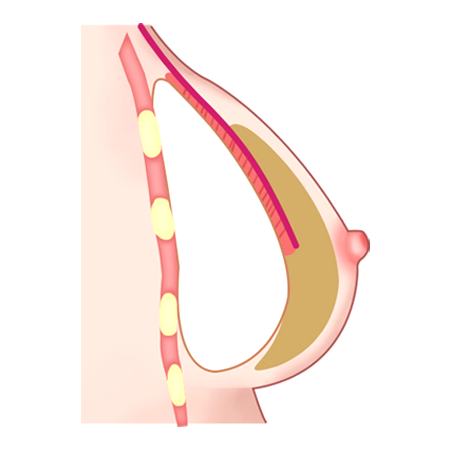

ผ่าตัดส่วนล่างของกล้ามเนื้อหน้าอกส่วนบน

เมื่อกรีดกล้ามเนื้อออก เนื่องจากแรงดึงของกล้ามเนื้อ ทำให้ส่วนบนของกล้ามเนื้อหดตัวและด้านล่างของกล้ามเนื้อจะยึดติดกับด้านล่าง

ใส่ซิลิโคนระหว่างกล้ามเนื้อที่ถูกกรีด ส่วนบนของซิลิโคนอยู่ด้านล่างของกล้ามเนื้อหน้าอก ส่วนล่างของซิลิโคนอยู่ด้านบนของกล้ามเนื้อหน้าอก

วิธีการใส่ท่อนบนของซิลิโคนลงไปใต้กล้ามเนื้อ และท่อนล่างลงไปใต้เยื่อกล้ามเนื้อ

ด้วยวิธีการผ่าตัดแบบเดียวกันนี้

ดึงส่วนบนของกล้ามเนื้อขึ้น

กล้ามเนื้อส่วนล่างจะยึดติดกัน

เทคนิคแบบ Dual Plane กล้ามเนื้อหดตัวลงและเคลื่อนที่ขึ้น

ผิวหนังและเนื้อเยื่อที่เชื่อมต่อกันค่อนข้างยืดได้ดี จึงสามารถสร้างเส้นโค้งตามธรรมชาติได้